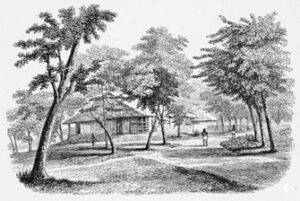

এবার আমরা বাড়ির দিকে এগোলাম। বাড়ির পেছনের দিকের মাঠ দিয়ে, অর্থাৎ হ্রদের উত্তর-পূর্ব দিক দিয়ে প্রবেশ করলে প্রথমেই একটা খড়ে ছাওয়া দেহাতী দেখতে ইঁট আর কাঠের বানানো একটা আস্তাবলখানা চোখে পড়বে। আস্তাবলের ভেতরে দুদিকে দুসারি ঘোড়া রাখার কুঠুরি রয়েছে। সংখ্যায় মোট ষোলটা। তার মধ্যে এখন ছখানা কুঠুরি দখল হয়ে আছে।

আস্তাবল

এখানে একবার ঢুকে ঘোড়াগুলোকে ভালো করে দেখে, তাদের মাথায় হাত বুলিয়ে, গায়ে চাপড় মেরে আদর টাদর করে আমরা পায়ে হেঁটে এগিয়ে গেলাম। নদীর ধার ধার ছায়াঢাকা পথ ধরে মোটামুটি পঞ্চাশ গজ এগিয়ে গেলে একটা ইঁট আর পাথরের বেশ বড়সড় মজবুত বাড়ি পাওয়া যাবে। তার মাথাটা পুরু করে খড়ে ছাওয়া, ঘরে খুব সুন্দর আলো বাতাস খেলে। এটা মূলনাথ হাসপাতালের পুরুষ বিভাগ।

হাসপাতাল, পুরুষ বিভাগ

এই বাড়িটি এই গৃহের কর্তা ১৮৪২ সালে বানিয়ে দিয়েছেন, অংশতঃ নিজের খরচেই। বাড়িটা বানানো হয়ে গেলে তিনি সরকারের কাছে সাহায্যের জন্য আবেদন করেন। সরকার হাসপাতালে বিনামূল্যে ওষুধ সরবরাহ করতে সম্মত হয়। কিন্তু তারা মিঃ এফ— কে শর্ত দেয় যে তাঁকে গ্যারান্টি দিতে হবে যে তিনি বাকী সমস্ত খরচ তিনি দেবেন, এমনকি একজন দেশীয় সহকারী সার্জেন যিনি থাকবেন, তার মাইনের অর্ধাংশও তিনিই দেবেন। মাইনের বাকী অর্ধাংশ দেবে সরকার। মিঃ এফ— এই সমস্ত শর্তে রাজী হয়ে যান। তারপর এক মুহূর্তও সময় নষ্ট করা হয় না। কলকাতা মেডিক্যাল কলেজ থেকে মাসে একশ টাকা মাইনে দিয়ে (পরে তা বেড়ে দেড়শ হয়) একজন সহকারী সার্জেনকে আনা হয়। মাননীয় কোম্পানী বাহাদুর হাসপাতালকে ওষুধপত্র আর সার্জিকাল যন্ত্রপাতি দেয়। হাসপাতালের দরজা দরিদ্র মানুষদের জন্য খুলে যায়। শুধুমাত্র মূলনাথের অন্তর্গত এলাকাতেই দুই লক্ষ চাষী রয়েছে! আর যদি আমি তোমাদের বলি যে এখান থেকে সবচেয়ে কাছের হাসপাতাল হল একদিকে কলকাতা, বাহান্ন মাইল দক্ষিনে, অন্যদিকে কৃষ্ণনগর, বত্রিশ মাইল উত্তরে, সুতরাং বুঝতেই পারছ, এই হাসপাতাল খোলাটা মূলনাথ আর তার আশেপাশের এলাকার মানুষজনের কাছে কী পরিমান আশির্বাদ হয়ে এসেছিল!

হাসপাতালের পুরুষ বিভাগে চব্বিশটি বেড রয়েছে। সবকটিই প্রায় সবসময় ভর্তি থাকে। আশেপাশের পরিবেশ অত্যন্ত স্বাস্থ্যকর হওয়া সত্ত্বেও যে রোগগুলো এখানকার দরিদ্র মানুষদের মধ্যে, বিশেষ করে চাষীদের মধ্যে সবচেয়ে বেশি করে দেখা যায় সেগুলি হল, জ্বর, প্লীহা আর আমাশা। রোদে-জলে ঘুরে বেড়ানো, দারিদ্র্য, খাদ্য-বস্ত্র–বাসস্থানের অভাব, এগুলিকেই মোটামুটি এই সমস্ত রোগের প্রাথমিক কারণ হিসেবে শনাক্ত করা যায়। তার ওপর এরা শুরুর দিকের লক্ষণগুলি মূর্খের মত অবহেলা করে (একথা নিশ্চিতভাবেই বলা যায় যে কলেরায় যত লোক মরে তার অর্ধেকের বেশী মরে এই অবহেলা করার জন্য), বিশেষ করে ডাক্তারের কাছে আসতে মারাত্মক দেরী করে। সংক্ষেপে বলতে গেলে, যতক্ষণ না তাদের শরীরের গড়বড়ের মাত্রা আশঙ্কাজনক হয়ে যায়, ততক্ষণ তাদের পাত্তা পাওয়া যায় না। এইসব কারনেই হাসপাতালে এক একটা রোগী একেবারে মারাত্মক শোচনীয় অবস্থায় আসে। এখানে সার্জিকাল কেসও আসে। নিয়মিত এবং যথেষ্ট পরিমানেই আসে। এই বিভাগে যে ইংরেজী শিক্ষায় শিক্ষিত ডাক্তারবাবুটি রয়েছেন, তার ওপর দেশী লোকেদের অগাধ বিশ্বাস ও বিস্ময় রয়েছে।